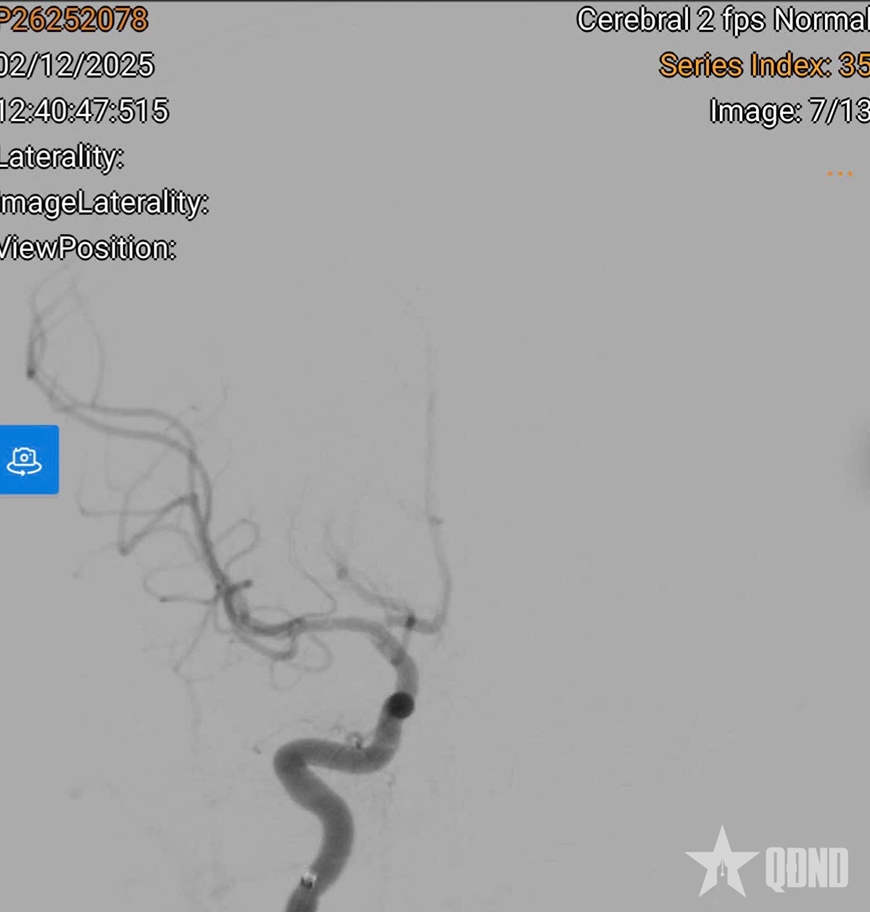

Bệnh nhi được can thiệp cấp cứu, nong bóng và đặt stent để tái thông mạch. Nhờ được đưa đến bệnh viện sớm, em D.K đã hồi phục gần như hoàn toàn, không để lại di chứng thần kinh.

| Hình ảnh sau khi can thiệp đặt stent cho bệnh nhi đột quỵ não. |